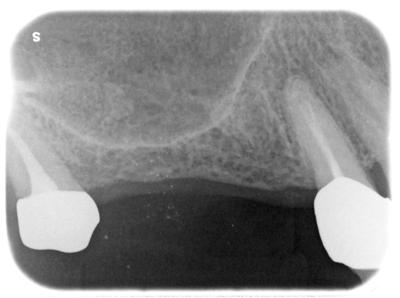

ヒーリングアバットメント装着

この後治癒を待ち、プロビジョナルを装着、同部をアンカーとして矯正治療(インビザラインではない)がスタート予定。

遠方からの通院だが、治療はまだまだ続く。